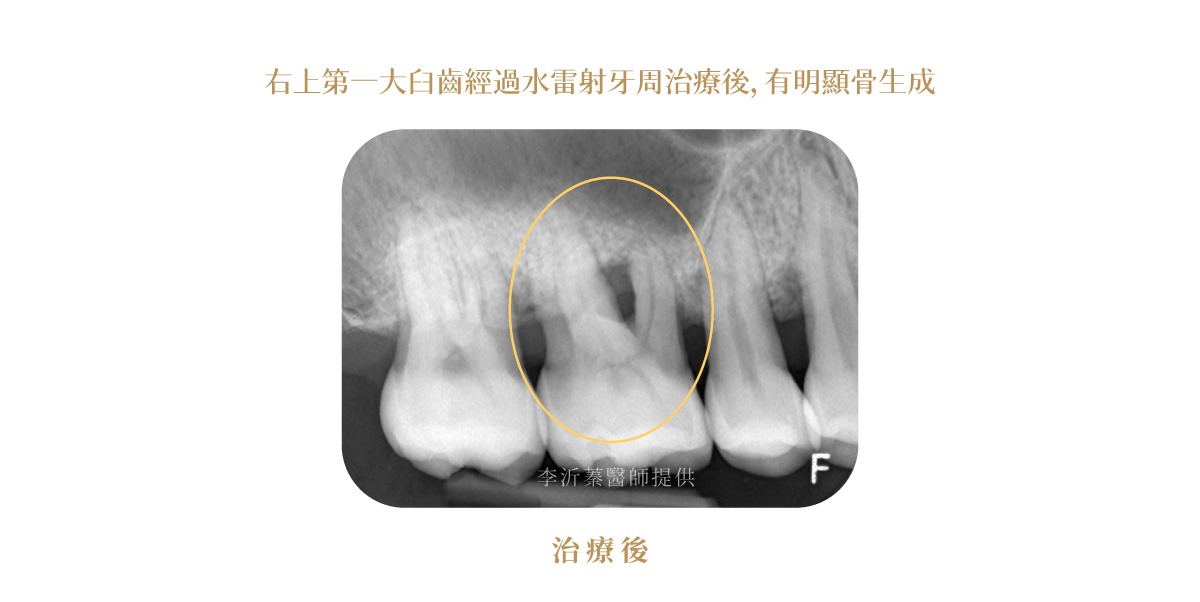

水雷射牙周治療案例